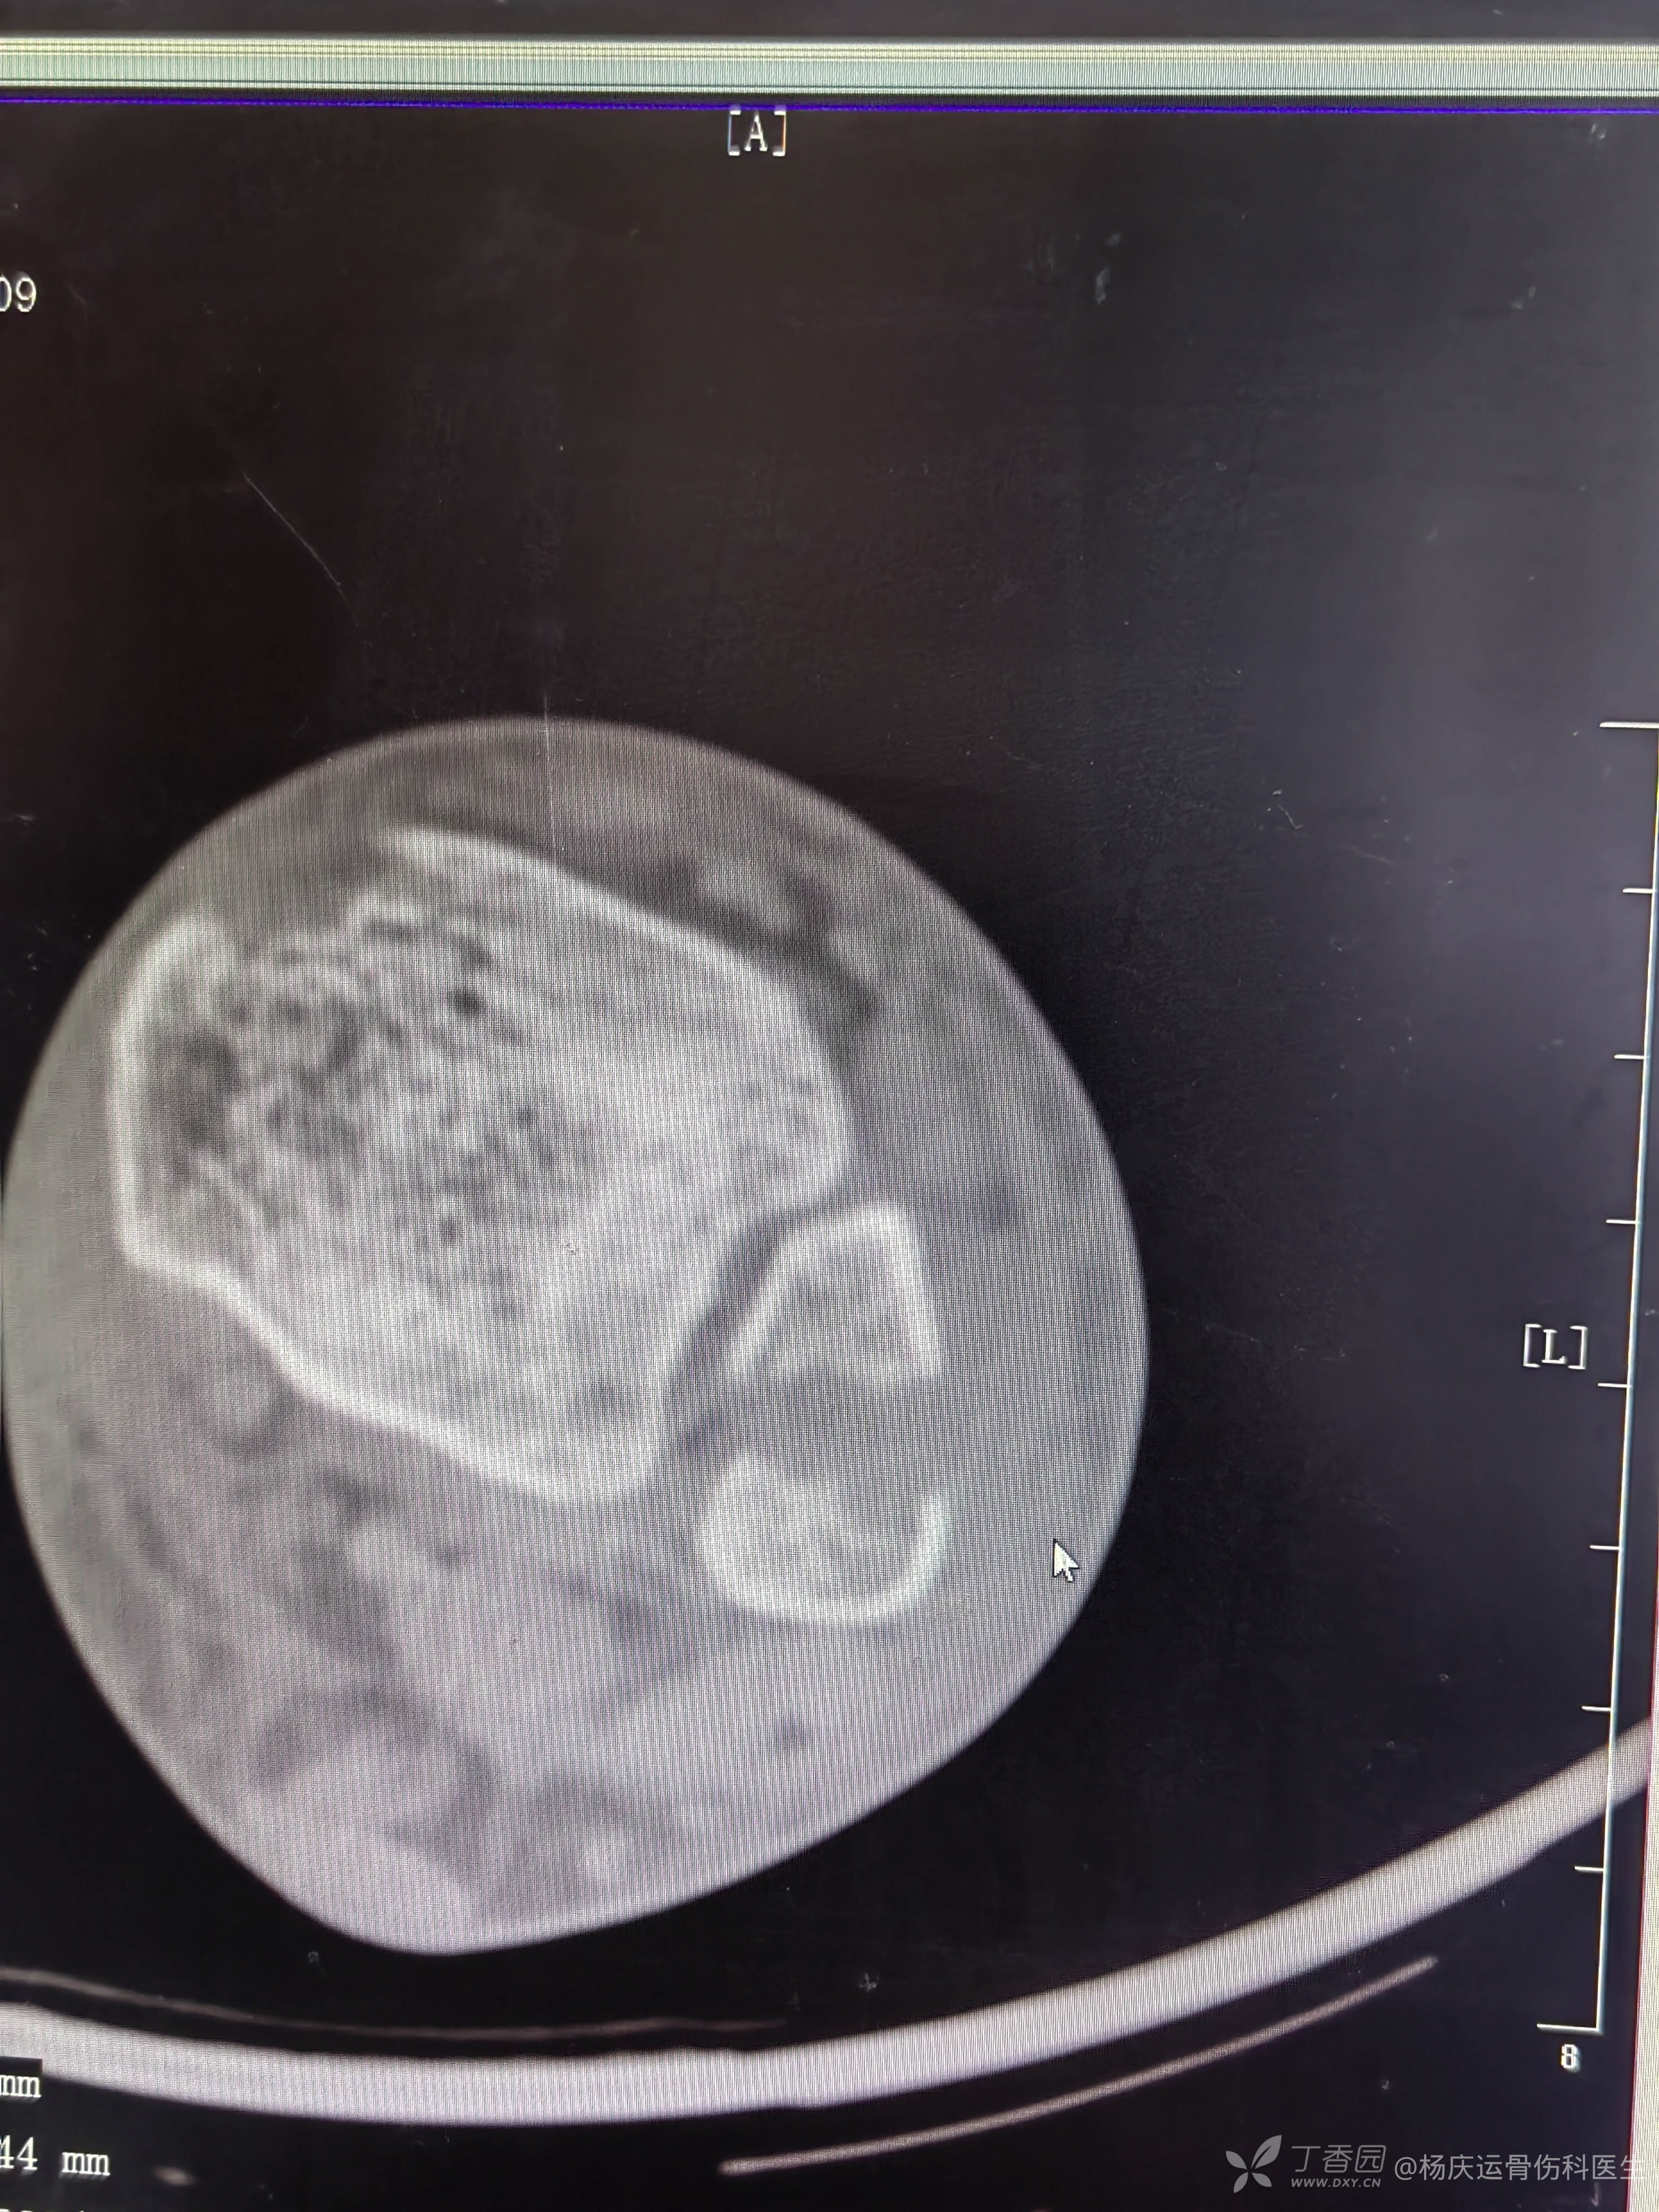

复位前CT